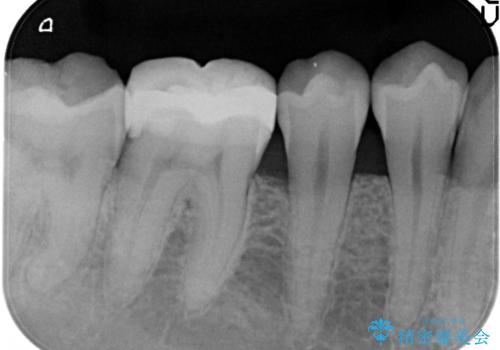

- 以前治療した右下の奥歯の歯の中が虫歯になっている気がするとのことで来院されました。

レントゲン上と視診上では確認できなかったのですが、患者様の希望もあり、一度かぶせ物を外して内部を確認し、オールセラミックを再度装着する計画としました。